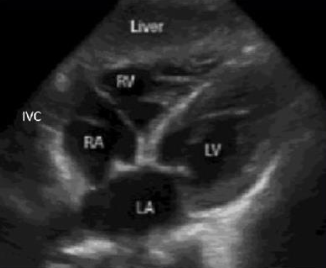

what view is this

subcostal 4 chamber